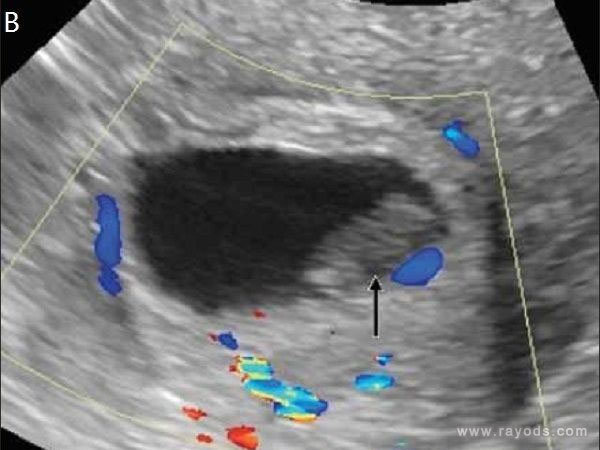

一般在怀孕5-6周,就可以透过B超清楚的看到卵黄囊的样子,其可以用来确认是否为宫内妊娠,而后随着胚胎生长发育,开始出现胎芽和胎心搏动,通常卵黄囊的形成最迟不超过8周,否则提示为孕囊发育不良,医生会建议终止妊娠。

怀孕5周通过B超可以测出卵黄囊

对于月经规律的女性,28-30天月经周期,正常怀孕40天左右,也就是5-6周就可以看到卵黄囊,不过有的胚胎发育比较慢,卵黄囊的形成时间稍晚,但最迟不超过8周,如果在第8周还未看到其结构,那么就需要结合血HCG化验及孕酮的情况,看是否需要终止妊娠。

从卵黄囊的形成过程来看,在妊娠第四周,卵黄囊囊壁形成3层细胞结构,到第五周囊壁就可清晰分辨出2个腔室,从第6周后卵黄囊囊壁开始表现出退化征象。

B超下卵黄囊消失

卵黄囊消失在孕8周

1孕5周卵黄囊大小达到顶峰,透过B超可清楚的看到其结构形状;2孕6周卵黄囊囊壁开始表现出退化征象,大小逐渐变小;3孕8周,卵黄囊不断变小然后形成仅有直径5mm左右的小泡残存在胚胎表面。